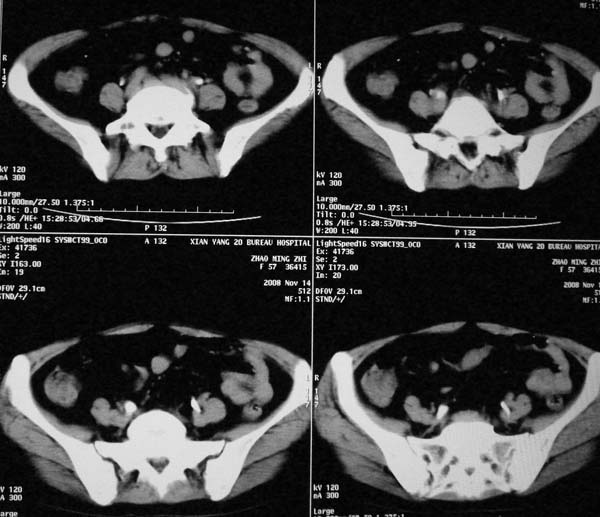

以下是引用dr.yang在2008-11-9 21:56:00的发言:[br]右肾上极占位?建议增强

以下是引用x-man在2008-11-9 22:30:00的发言:[br]建议先增强,右肾影明显增大,上极见边不清低密度肿块影,肿瘤待定.

以下是引用卜一在2008-11-10 8:09:00的发言:[br]建议先增强,右肾影明显增大,上极见边不清低密度肿块影,肿瘤待定.支持!另:第一次碎石是否肾受到损伤?合并感染?不知第一次碎石前是否做过彩超?

以下是引用dsl555在2008-11-9 23:57:00的发言:[br]建议先增强,右肾影明显增大,上极见边不清低密度肿块影,肿瘤待定. [br] [br]